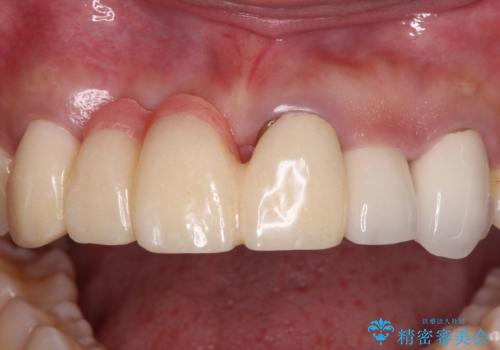

長く見える歯を治したい 歯肉移植による歯肉増大術

歯肉が痩せてしまっている状態を改善するため、口蓋から歯肉の結合組織を採取し、移植することで厚みを増大させることとし、その後オールセラミックブリッジにて補綴治療を行うこととしました。